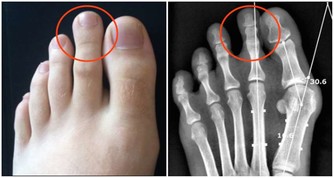

痛風患者能吃魚肉嗎?

想要判定痛風患者能不能吃魚肉,就要看魚肉是不是含有高嘌呤物質。魚的種類有很多種,像一些沙丁魚、鳳尾魚、小乾魚等這類含有高嘌呤物質,建議痛風患者最好不要食用。

而像我們經常見的鱸魚、鯉魚、鯽魚、鱔魚等屬於中等嘌呤物質,是可以少吃的。三文魚、金槍魚屬於中低嘌呤魚類,也是可以適量吃。